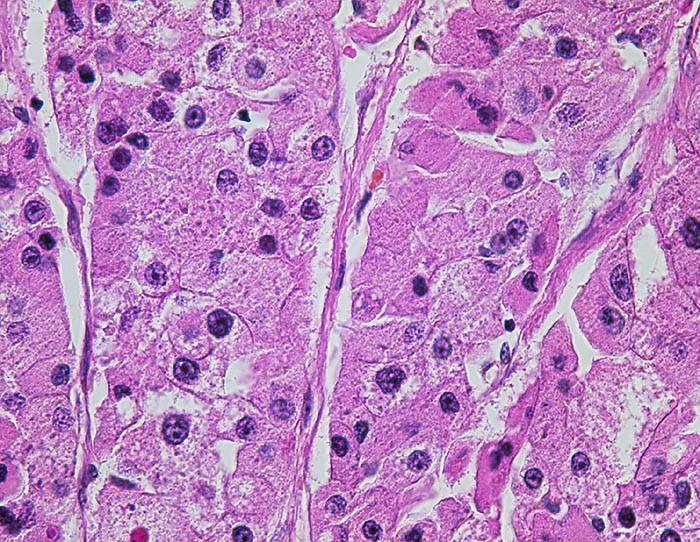

Hepatozelluläres Karzinom : Ovarmetastase

Trabekulär angeordnete leberähnliche Tumorzellen mit nur geringen Kernatypien.

Klarzellige und sarkomatoide Tumorareale.

St.n. Lebertransplantation wegen Hepatozellulärem Karzinom bei Zirrhose und chronischer Hepatitis C vor 2 Jahren. Jetzt Metastasen von 12 und 14cm Durchmesser in beiden Ovarien.